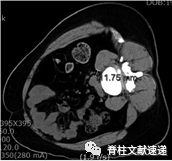

图示:术前测量手术通道。患者右侧卧位时L4–L5节段的CT轴位图。

图示:皮肤切口位置的术前计划。患者右侧卧位时L4–L5节段的CT轴位图。A线切向穿过椎体前壁。B线表示理想的载体,将cage放置在椎间隙中,进一步实现角度调整。

图示:腰椎MRI轴位图显示OLIF手术路径。黄色块代表管状牵开器。红色区域是腰肌向内侧冠状面收缩所获得的空间(红色箭头)。